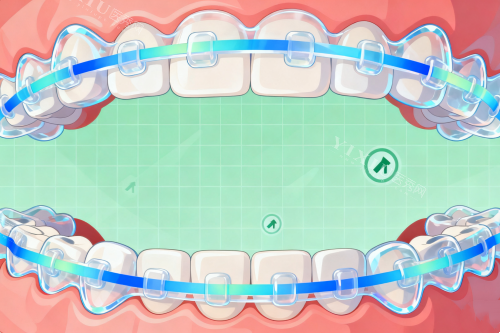

终于轮到我了,我跟着导医小姐姐来到了医生的诊室。给我看诊的是一位姓王的医生,王医生特别和蔼可亲,他先让我躺在治疗椅上,然后开始给我检查牙齿。他一边检查,一边跟我讲解我的牙齿情况,说得特别详细,什么牙齿排列不整齐、咬合关系不正常之类的,我虽然不太懂,但也能大概明白我的牙齿问题挺重的的。检查完之后,王医生根据我的牙齿情况,给我制定了好几种矫正方案,有传统的金属托槽矫正,还有隐形矫正。他耐心地给我分析了每种方案的优缺点,还结合我的个人需求和经济情况,推荐我做隐形矫正。他说隐形矫正美观度高,几乎看不出来戴了矫正器,而且对日常生活的影响比较小。我听了王医生的介绍,觉得隐形矫正挺适合我的,就决定采用这个方案。

过了几天,我接到了郑州马泷齿科的电话,说矫正方案已经确定好了,让我过去试戴矫正器。我迫不及待地赶到了诊所。见到王医生后,他又跟我详细地讲了一下矫正方案的细节,还教我怎么佩戴和摘取矫正器,以及矫正期间的注意事项。我戴上矫正器之后,感觉还挺舒服的,没有那种特别紧勒的感觉。王医生仔细地检查了矫正器的佩戴情况,调整了一下,确保矫正器和我的牙齿贴合得很不错。

从那之后,我就开始了漫长的牙齿矫正过程。每隔一段时间,我就要去郑州马泷齿科复诊一次。每次复诊,王医生都会认真地检查我的牙齿矫正情况,根据牙齿的移动情况调整矫正器。他还会跟我聊聊我的日常生活,问问我戴矫正器有没有什么不舒服的地方,让我感觉特别温暖。护士小姐姐们也会在旁边提醒我一些注意事项,比如要按时刷牙、保持口腔清洁、避免吃太硬的食物等等。